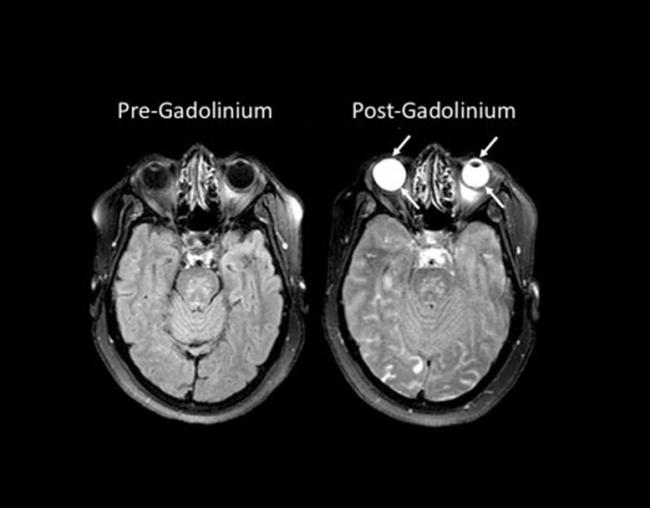

The eyes glowed so brightly on those images due to gadolinium, a harmless, transparent chemical often given to patients during magnetic resonance imaging (MRI) scans to highlight abnormalities in the brain. In healthy individuals, gadolinium remains in the blood stream and is filtered out by the kidneys. However, when someone has experienced damage to the blood-brain barrier, which controls whether substances in the blood can enter the brain, gadolinium leaks into the brain, creating bright spots that mark the location of brain damage.

The researchers performed MRI scans on 167 stroke patients upon admission to the hospital without administering gadolinium and compared them to scans taken using gadolinium two hours and 24 hours later. Because gadolinium is transparent, it did not affect patients’ vision and could only be detected with MRI scans. Roughly three-quarters of the patients experienced gadolinium leakage into their eyes on one of the scans, with 66 percent showing it on the two-hour scan and 75 percent on the 24-hour scan. The phenomenon was present in both untreated patients and patients who received a treatment, called tPA, to dissolve the blood clot responsible for their strokes.